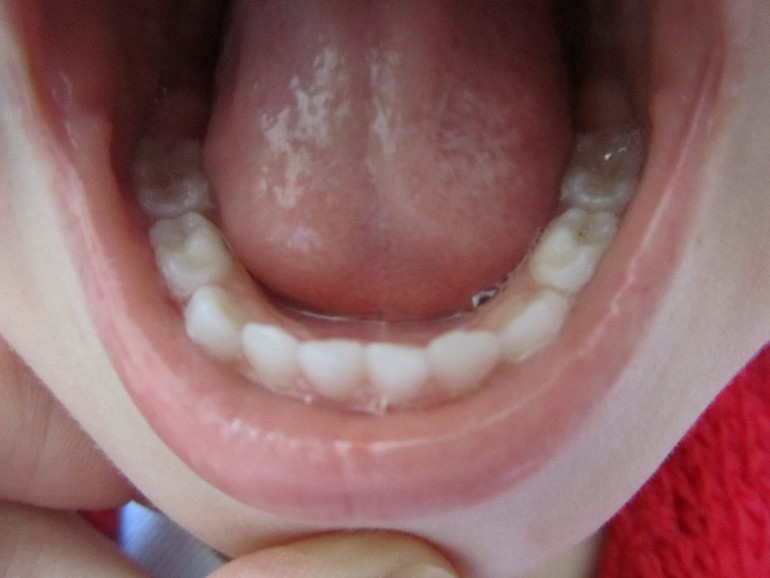

И еще, на жевательном нижнем левом зубе (честно, не знаю как он называется) мне кажется или там маленькая коричневая точечка это тоже кариес? Может нужно полечить пока он совсем маленький?

Вроде на мой неопытный взгляд остальные зубки в норме?